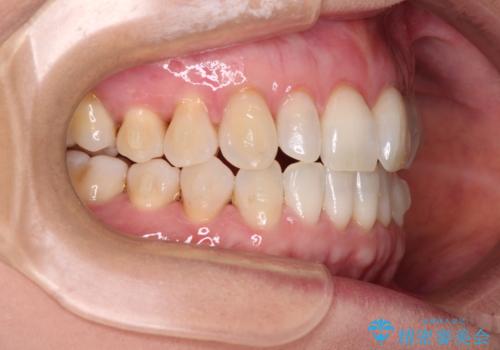

前歯のスペースが気になる インビザラインによる矯正治療

- 前歯の上下スペースによる食べにくさを気にして来院された患者様です。

インビザラインにより上下の前歯の隙間を閉じていくこととしました。

舌の突出癖があると上下前歯にスペースが開くため、矯正治療を機会に舌癖を改善するトレーニングを行ってもらい、矯正治療後の後戻りを防止するように指導しています。